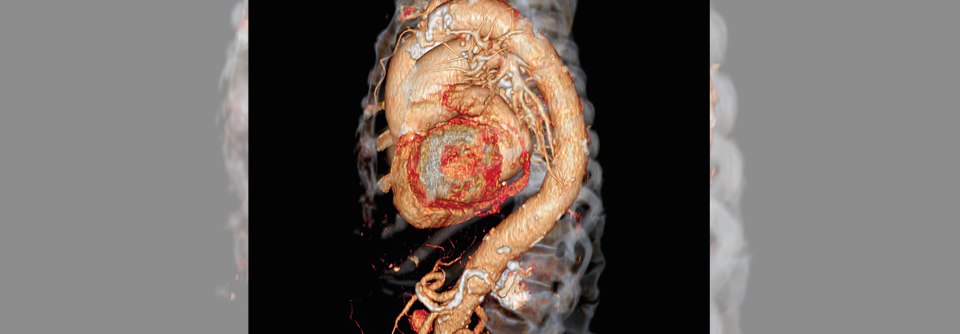

Bei gut einem Viertel der Patientinnen hatte man das erweiterte Gefäßsegment chirurgisch per Laparotomie ausgeschaltet (statt über die von den Leitlinien empfohlene endovaskuläre Intervention) – jedoch nur bei etwa einem Sechstel der Männer. Nach Korrektur für statistische Störfaktoren lag bei Frauen die Wahrscheinlichkeit für eine offene OP immer noch um etwa zwei Drittel höher als bei den Männern (Risk Ratio 1,65).

Da der Trend insgesamt Richtung endovaskulärer Aortenreparatur geht, sind die beobachteten Geschlechterunterschiede bei diesem Verfahren bedenklich, so die Autoren. Über die Ursachen der Differenzen könne man derzeit nur spekulieren. Möglicherweise existieren für Frauen einfach keine passenden Stentgrafts, da sich ihre Befunde anatomisch oft komplexer präsentieren – z.B. mit einem kürzeren und schmaleren Aneurysmahals.